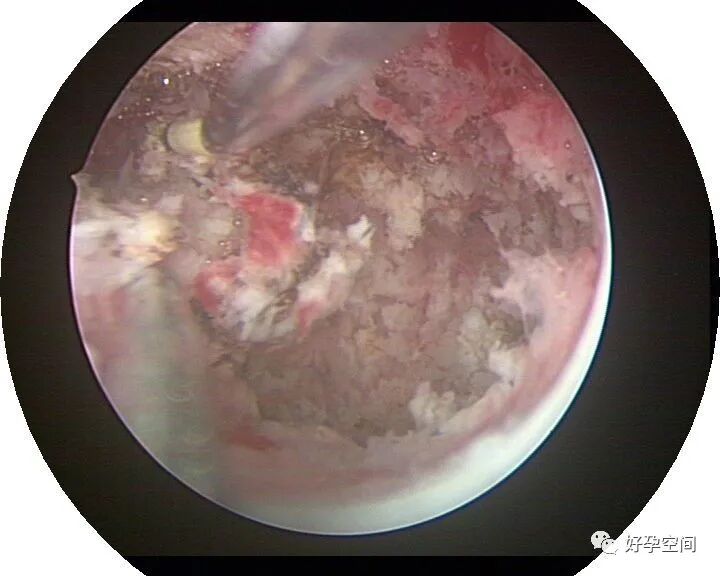

病例13:豆渣样干酪样坏死组织